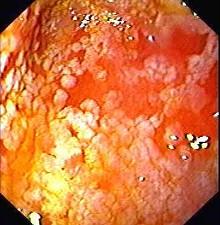

慢性萎缩性胃炎的病理特征是 ( )A、粘膜充血、水肿B、粘膜糜烂、出血C、粘膜肥厚D、粘膜广泛炎症细胞浸润E、肠腺上皮化生

问题 慢性萎缩性胃炎的病理特征是 ( )

选项 A、粘膜充血、水肿 B、粘膜糜烂、出血 C、粘膜肥厚 D、粘膜广泛炎症细胞浸润 E、肠腺上皮化生

答案 E